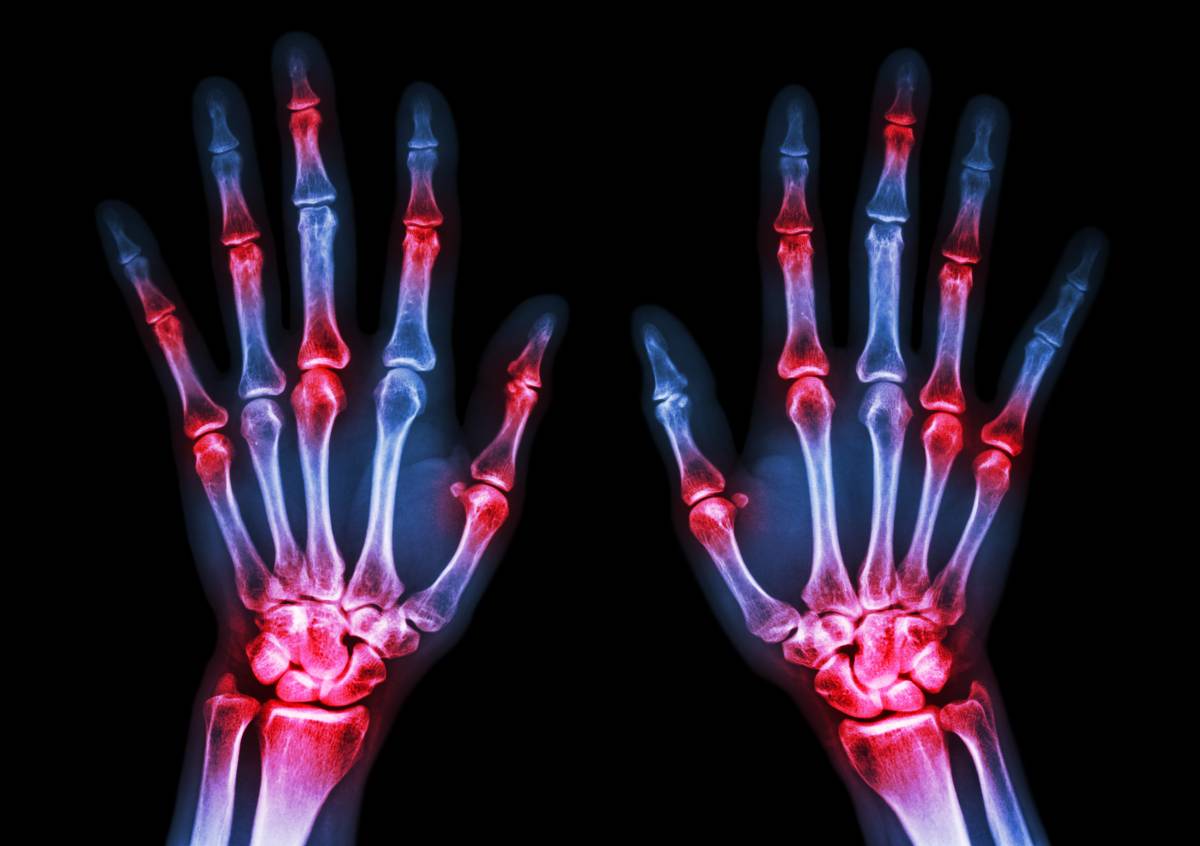

二是膝关节置换,主要针对的是膝关节骨性关节炎或者类风湿性关节炎等发展到终末期的关节病,需要做膝关节置换的情况。